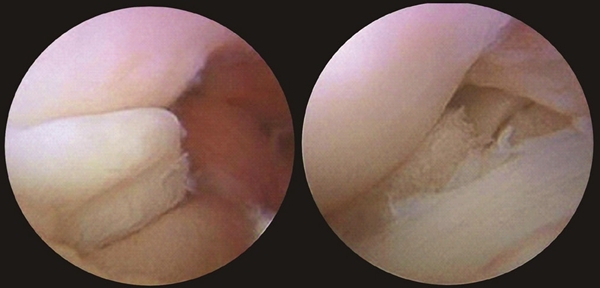

诊断的金标准是关节镜检查所见,而且关节镜下可以直接手术将损伤的盘状半月板切除。但关节镜为有创方法,作为诊断,临床一般用骨科查体配合MRI检查(图4-10-1-4)。

图4-10-1-4 膝关节镜下盘状半月板